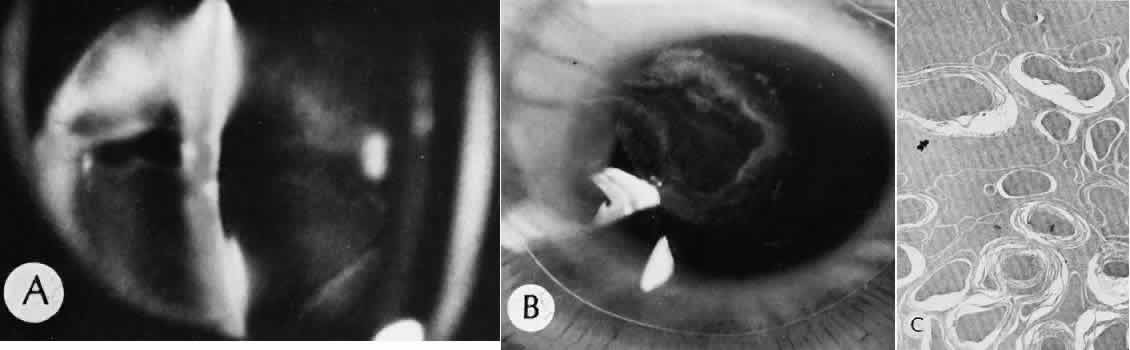

Iris cyst formation (Figs. 45 and 46 is also caused by implantation of surface epithelium onto the iris at the time of surgery or trauma. The cyst generally grows slowly and is accompanied by peripheral anterior synechiae. If extensive, the cysts may cause a secondary chronic closed-angle glaucoma. Histologically, the cyst is lined by stratified squamous or columnar epithelium, sometimes containing mucous cells, and is filled with keratin debris (white or pearly cysts) or mucous fluid (clear cysts).

Fig. 45. Two cases of epithelial iris cyst formation following cataract extraction. A. Instead of forming a flat sheet to cover the posterior cornea and the anterior iris, the invading epithelium has formed a cyst in the anterior chamber. The cyst usually retains some continuity with the original wound but also may become free-floating in the anterior chamber. B. In this case, there is extensive distortion of the iris. The type of ingrowth, sheet or cystic, is a major determinant of the method of treatment used. C. The histologic character of the cyst lining indicates the presence of goblet cells. The origin of these cells may have been from the conjunctiva. In this rare circumstance, the cyst may become filled with mucous. (Hematoxylin-eosin stain; × 101.)

Fig. 46. The contents of an epithelial cyst and the consequences of an epithelial presence. A. The histologic section of this case of epithelial ingrowth demonstrates the presence of both a Soemmering's ring cataract and an epithelial inclusion cyst. Squamous epithelium desquamates surface cells as part of its renewal process. In this case, the cyst is filled with desquamated debris. The desquamated debris, if liberated into the anterior chamber, will evoke an extreme inflammatory reaction similar to that encountered with a ruptured dermoid cyst of orbital soft tissue. (Hematoxylin-eosin stain; × 10.) B. High magnification of the cyst wall shows that the epithelium has become differentiated. The desquamating surface is clearly differentiated from the more primitive-appearing basal cells. Degenerated surface cells will fill the cyst cavity. The underlying stroma of the iris, originally diaphanous in character, has become coarse and compact because of the influence of the invading epithelial cells.